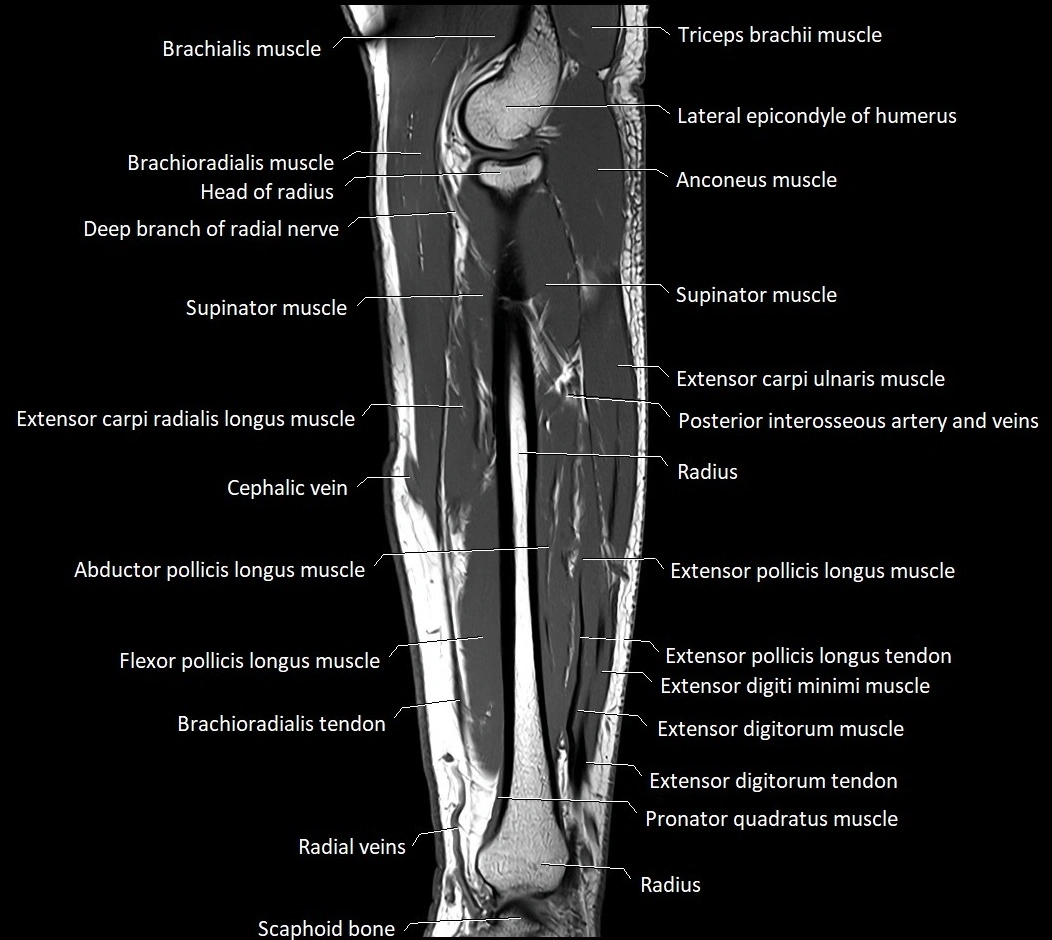

The abductor pollicis longus (APL) tendon is a strong, flat tendon that arises from the abductor pollicis longus muscle in the posterior compartment of the forearm. It is one of the key tendons of the first dorsal compartment of the wrist, alongside the extensor pollicis brevis (EPB) tendon. Its main function is to abduct and extend the thumb at the carpometacarpal (CMC) joint, assisting in grasp and pinch movements.

The APL tendon is highly variable and often has multiple slips, sometimes inserting onto both the base of the first metacarpal and the trapezium. Due to its close anatomical relationship with the EPB tendon within a tight fibro-osseous tunnel, the APL is commonly involved in De Quervain’s tenosynovitis, a painful inflammatory condition of the radial wrist.

Origin, Course, and Insertion

• Origin: Posterior surface of the ulna and radius, and the adjacent interosseous membrane, distal to the supinator muscle

• Course:

• Tendon forms in the distal third of the forearm and passes obliquely downward and laterally.

• Travels beneath the extensor retinaculum within the first dorsal compartment of the wrist.

• Often runs in a common synovial sheath with the extensor pollicis brevis tendon.

• Insertion:

• Main insertion on the lateral base of the first metacarpal bone.

• Accessory slips may insert into the trapezium, thenar fascia, or abductor pollicis brevis tendon.

Relations

• Anteriorly: Radial artery and tendons of the flexor carpi radialis and brachioradialis.

• Posteriorly: Radius and the insertion area of the extensor pollicis longus.

• Laterally: Extensor pollicis brevis tendon (in same compartment).

• Medially: Extensor carpi radialis longus and brevis tendons.

• Superiorly: Extensor retinaculum and subcutaneous tissues of the radial wrist.

MRI Appearance

• T1-weighted images:

• Tendon: Low signal (dark) continuous band extending to the first metacarpal base.

• Muscle belly: Intermediate signal.

• Surrounding fat: Bright, aiding tendon visualization.

• Pathology: Tendon thickening, irregularity, or focal intermediate signal in tendinopathy.

• T2-weighted images:

• Normal tendon: Low signal intensity, darker than on T1.

• Surrounding sheath: Low to intermediate signal.

• Pathology: Bright hyperintense signal in or around tendon in tenosynovitis.

• Fluid in sheath: well-defined bright rim encircling tendon.